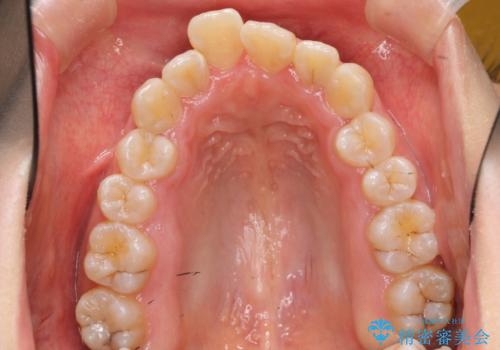

上下の前歯のがたつき 歯を抜かずに矯正

- 上下の前歯のがたつきを主訴に来院。

歯を抜かずに前歯を揃えています。

奥歯を後ろに下げたりなどはしていません。

奥歯を外に広げ、前歯中心に歯を少し削っていますが、健康には問題ない範囲で行なっています。